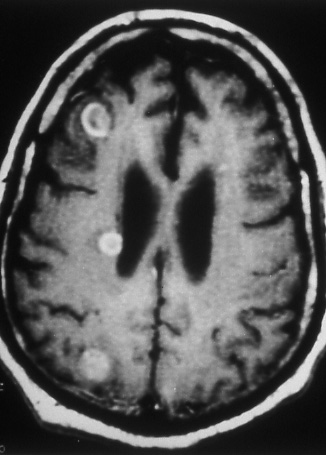

Fig.

29: M1 disease.

Three enhancing metastases

of lung cancer are present

in this contrast enhanced

T1 magnetic resonance

image of the brain. |

M1 designates metastasis to distant organ

and lymph node sites. It is used also to

designate discontinuous tumor lesions outside

the parietal pleura in the chest wall or

in the diaphragm, and to classify metastasis

in ipsilateral non-primary tumor lobe(s).